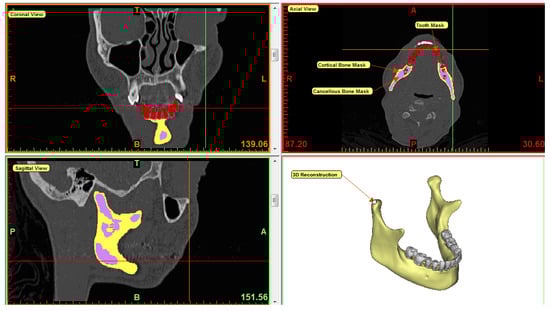

2.1. Image Acquisition

2.4. Subject-Specific FE Model Creation